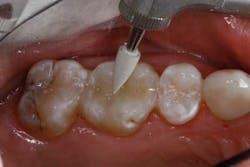

Fig. 6.

The depth of the cavity was determined to be 4 mm or less. The bulk-filled composite (Tetric EvoCeram® Bulk Fill) was placed in the preparation (Figs. 9 and 10). In this case, the first increment was placed, followed by additional material that was adapted to the tooth anatomy (Figs. 11 through 13). After further refining, the bulk-fill composite was light-cured in one increment for 10 seconds (1,200 mW/cm2).